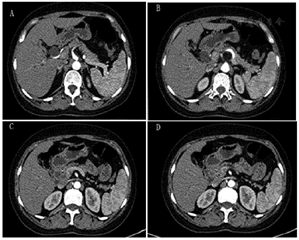

实验室AST: 114 U/L,ALT: 205 U/L,TBIL:141.10μmol/L, DBIL: 125.20μmol/L, IBIL:15.9μmol/L。AFP、CEA、CA125、CA199等肿瘤标志物均正常。腹部超声提示肝内及肝外胆管扩张。CT示胆总管下段占位性病变(图1)。MRCP提示胆总管中段局限性狭窄并肝内外胆管及胆总管上段扩张,不支持典型肿瘤性病变(图2)。ERCP提示胆总管远端正常,导丝无法通过胆总管下段(图3)。